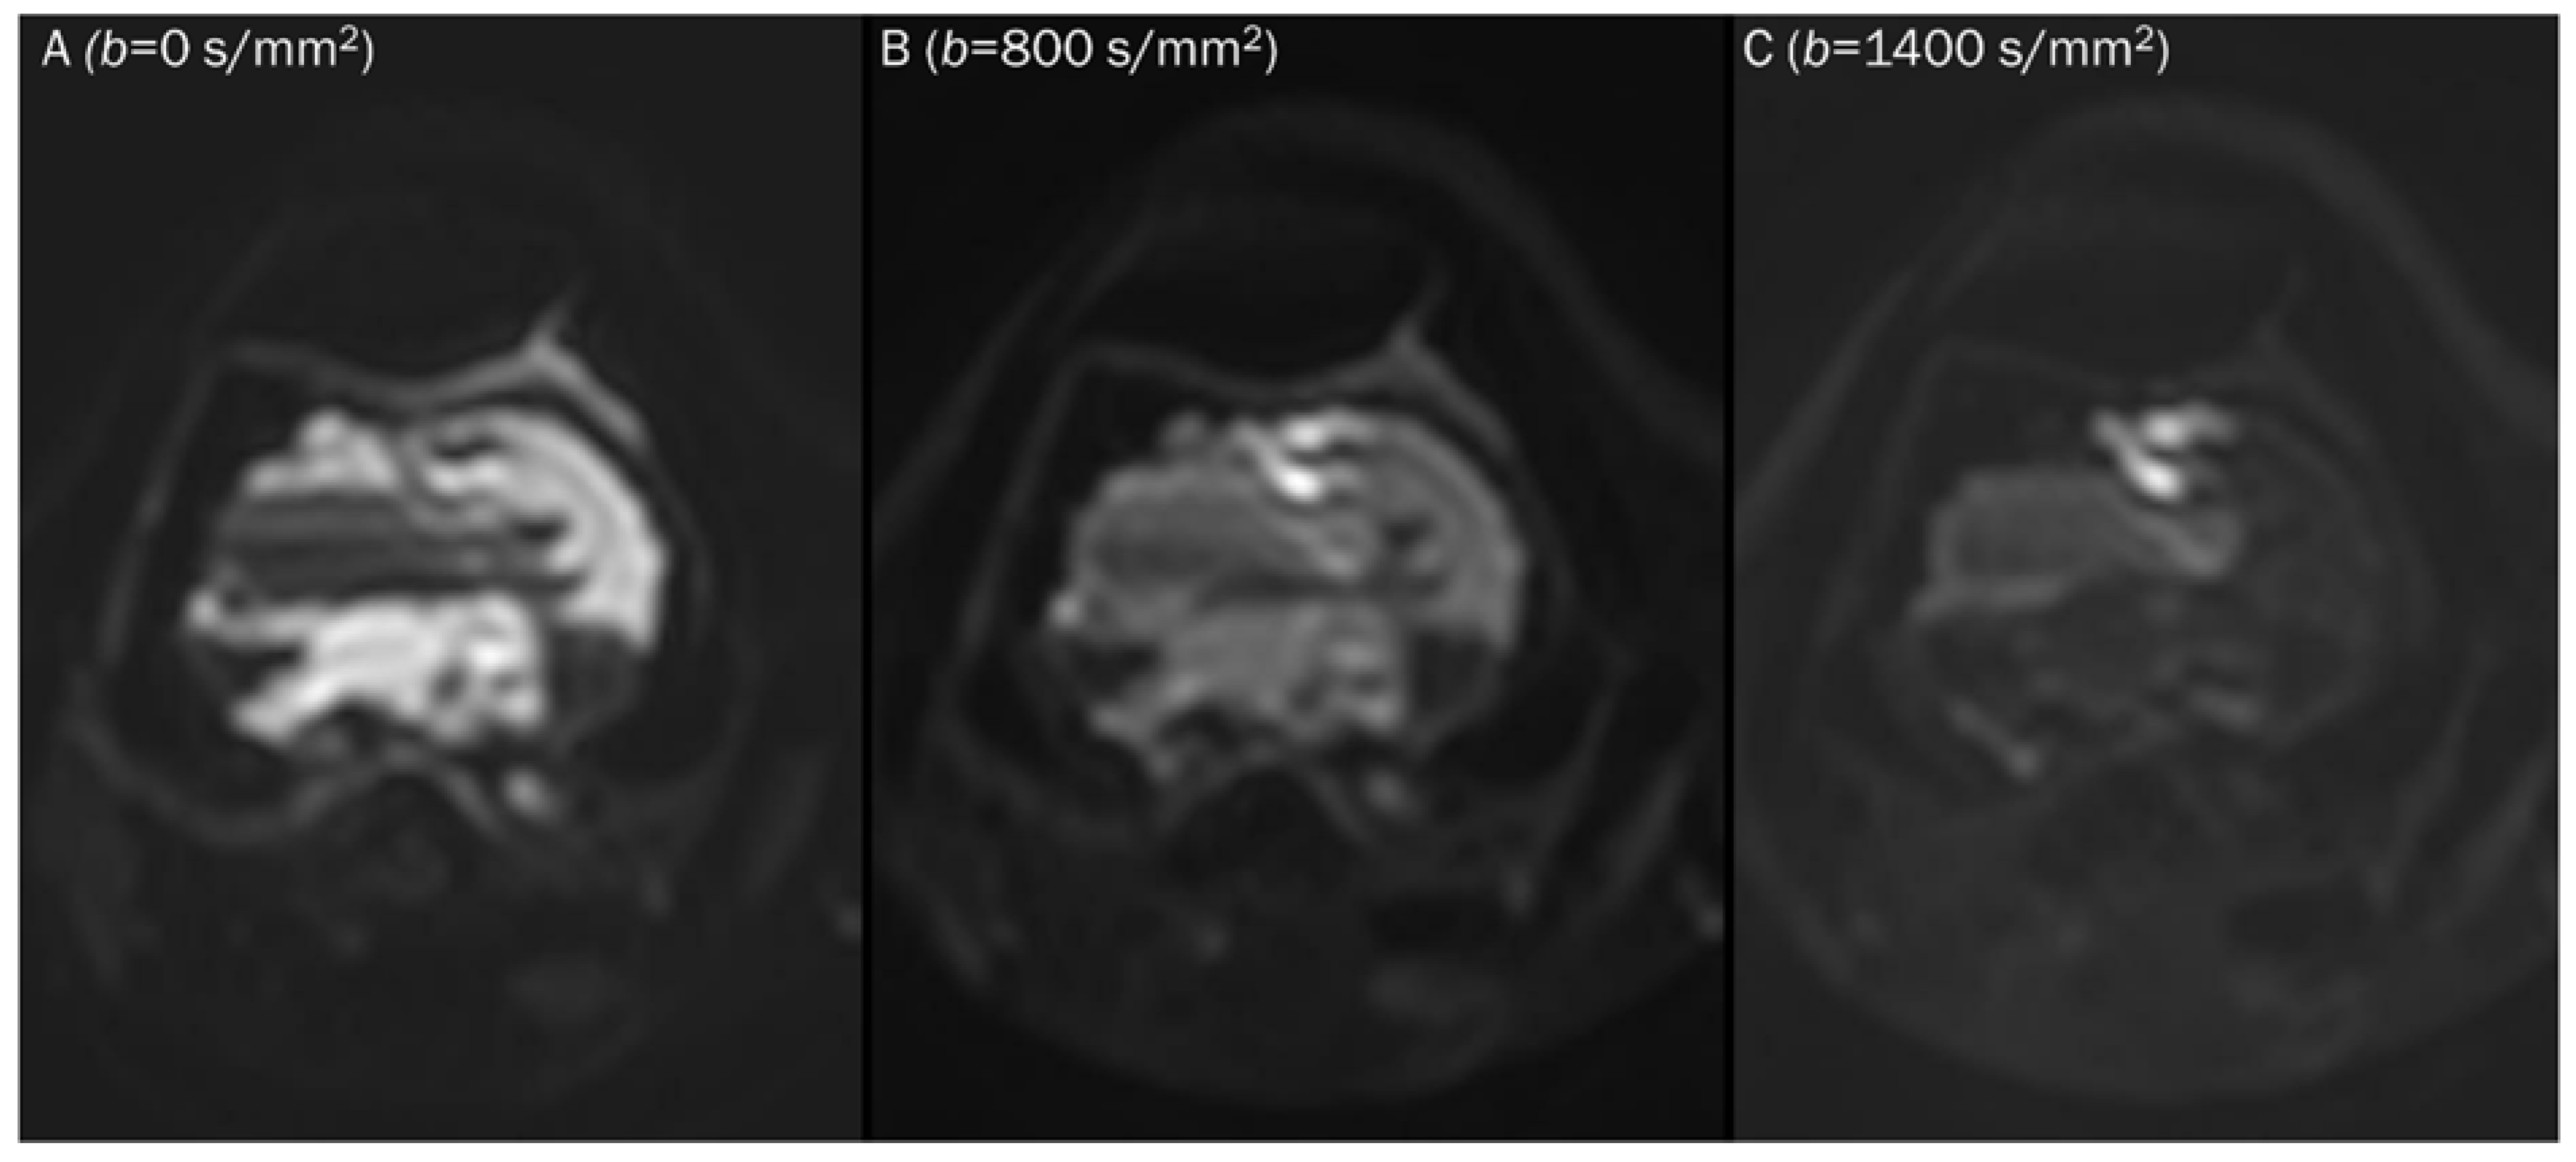

7.2. Hematoma